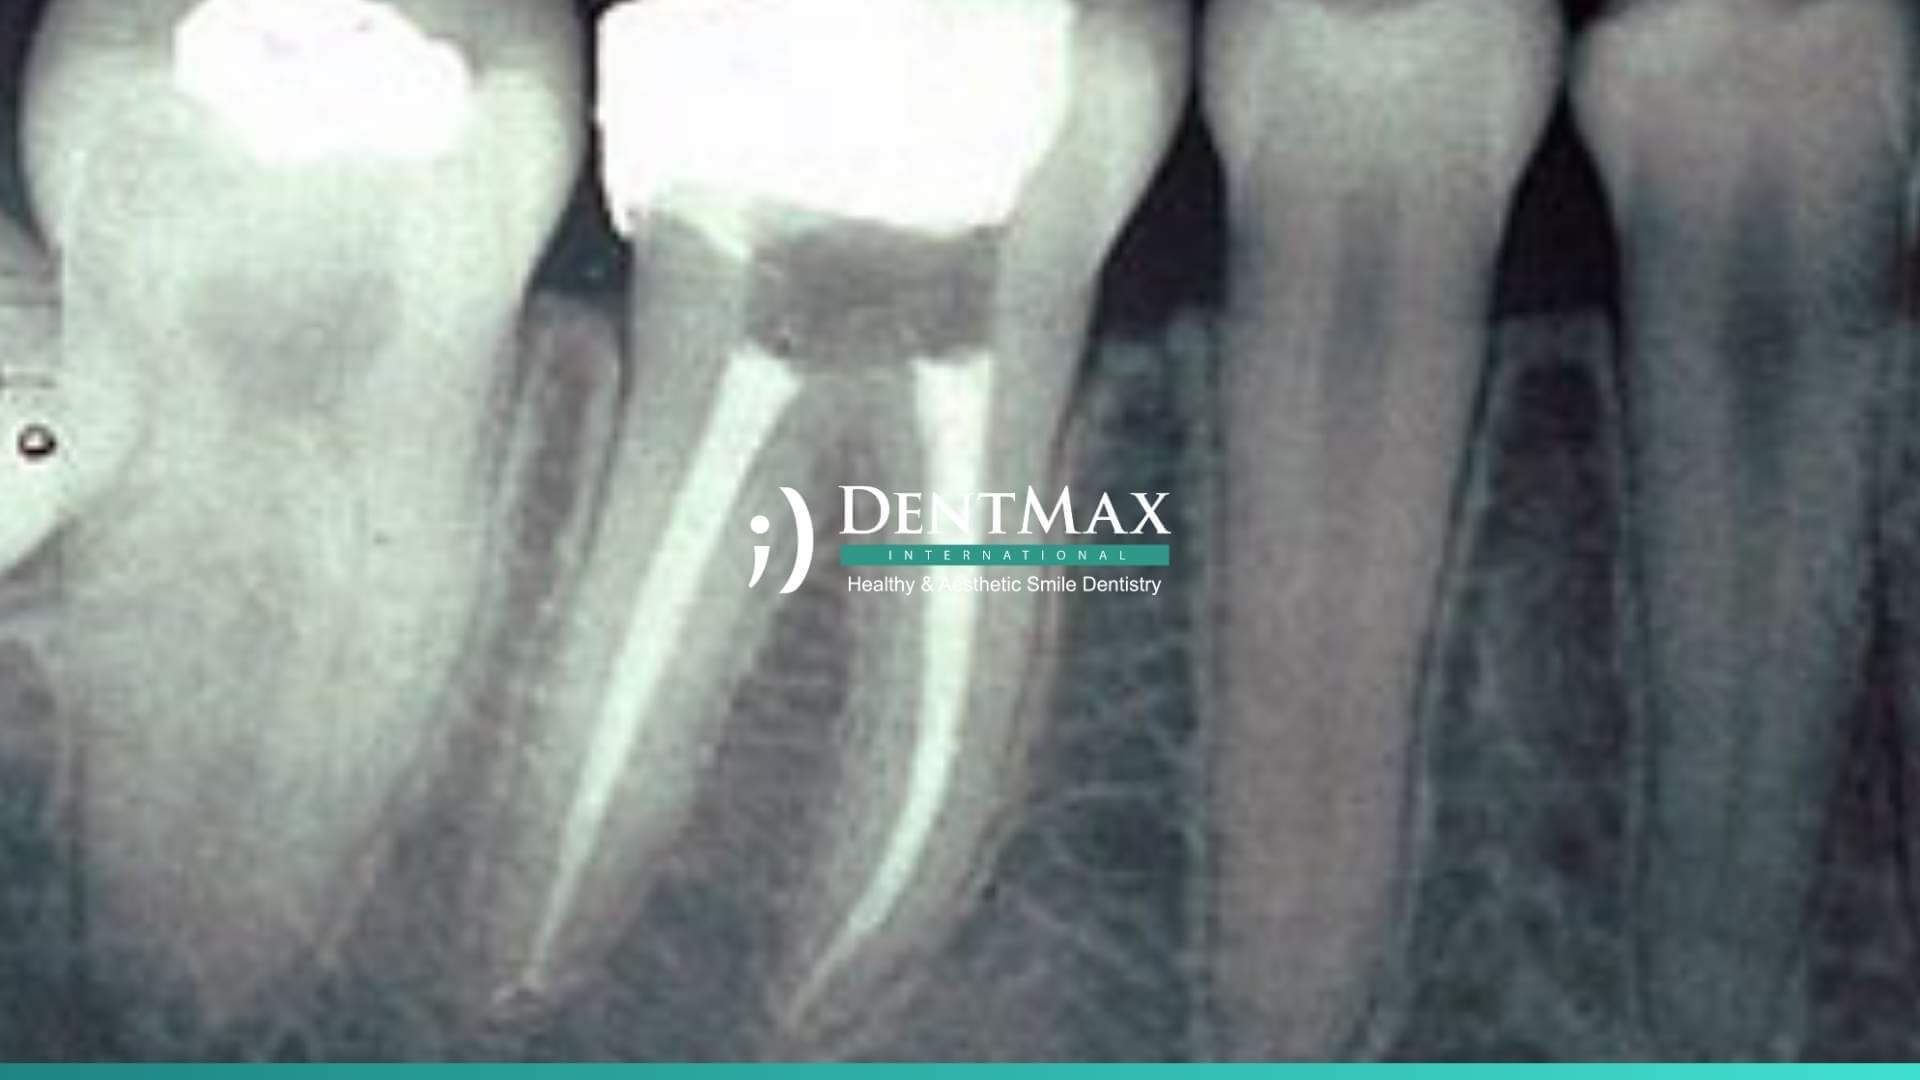

1. Muayene ve Röntgen: Diş hekimi, dişi muayene eder ve röntgen çekerek dişin durumunu değerlendirir.

5. Kök Kanallarının Doldurulması: Kanallar, özel bir dolgu maddesi ile doldurulur.

6. Kalıcı Dolgu veya Kuron: Dişin üzerine kalıcı bir dolgu veya kuron yerleştirilir.